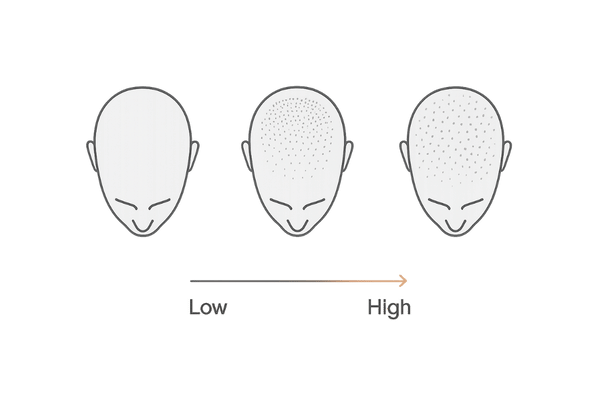

薄毛が進行している方の頭皮をサーモグラフィーで観察すると、健常な頭皮に比べて全体の温度が低かったり、温度に著しいムラが見られたりする傾向があります。

特に、薄毛が気になる部位(例えば、頭頂部や生え際)が他の部位に比べて低温であるケースが多く報告されています。

これは、その部位の毛細血管の血流が低下し、毛母細胞が栄養不足に陥っている可能性を示します。サーモグラフィーは、このような薄毛リスクの高い領域を視覚的に特定するのに役立ちます。

健康で血行が良好な頭皮は、サーモグラフィーで見ると、中心部から外側に向かってなだらかに温度が分布し、全体的に均一な暖かい色を示します。

特に、血管が太く血流量の多い側頭部は比較的高温になる傾向があります。左右の温度差が少なく、極端な低温部分が見られないことが、正常な状態の一つの目安となります。

血行不良の頭皮には、いくつかの典型的な特徴が現れます。最も一般的なのは、薄毛が進行しやすい頭頂部や前頭部が、血流の保たれやすい側頭部や後頭部に比べて明らかに低温になるパターンです。

頭皮の部位によって血行のしやすさには違いがあり、それが温度差として現れます。側頭部や後頭部は、筋肉の動きが比較的多く血管も太いため、血流が保たれやすく温度が高い傾向にあります。

一方、頭頂部は帽状腱膜という硬い膜で覆われており、筋肉が少なく血管も細いため、血流が滞りやすく温度が低くなりがちです。

この部位ごとの温度差が極端に大きい場合、それは血行不良が進行しているサインであり、特に男性型脱毛症(AGA)のリスク評価において重要な指標となります。

特に、長期間にわたって頭頂部などが慢性的な低温状態にある場合、その部位の毛髪は徐々に細くなり、成長期が短縮され、最終的には抜け落ちてしまいます。

サーモグラフィーで低温エリアを特定することは、どの部位が最も薄毛のリスクにさらされているかを把握し、重点的なケアを行う上で非常に有効です。